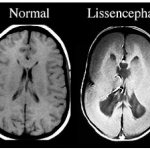

• врожденные пороки развития головного мозга;